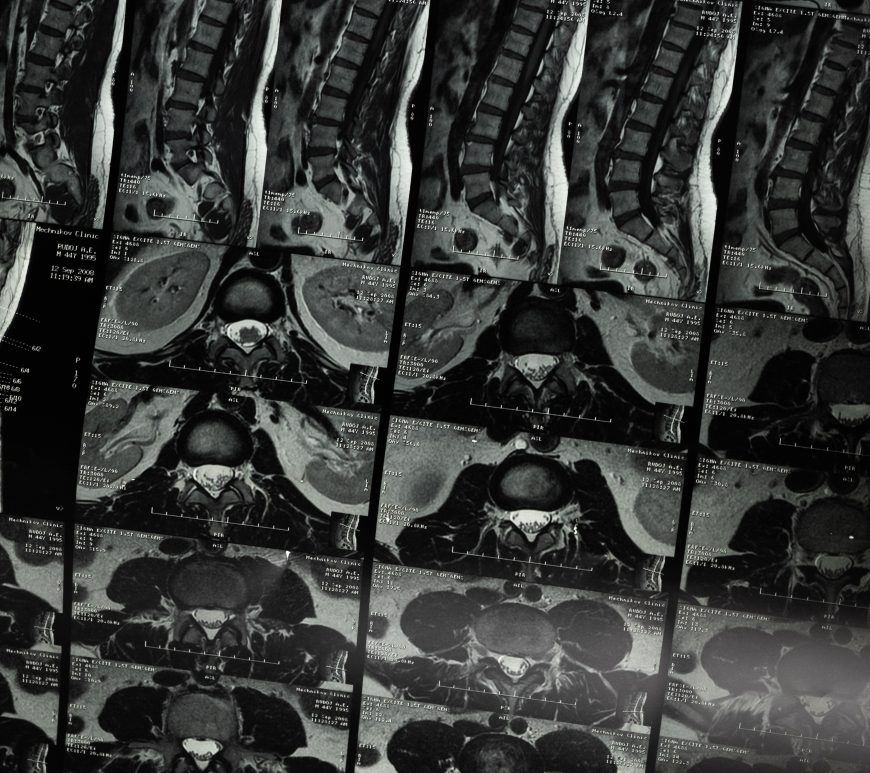

The majority of symptomatic disc herniations are found at the lower two lumbar interspaces, that is, about 50% at L4–5 and 47% at L5-S1 (1). The remaining 3% are found at higher lumbar levels (1). A r...